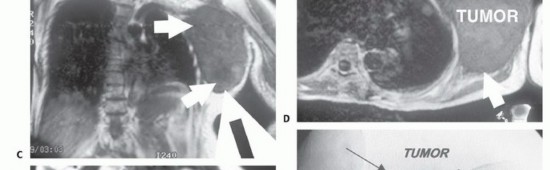

لفهم جراحة استئصال أورام الكتف مع الحفاظ على الطرف، من الضروري أولاً فهم التشريح المعقد لهذه المنطقة. حزام الكتف ليس مجرد مفصل واحد، بل هو منظومة معقدة من العظام، المفاصل، العضلات، الأربطة، الأوتار، الأعصاب، والأوعية الدموية التي تعمل بتناغم لتمكين الذراع من الحركة في جميع الاتجاهات. هذا التعقيد هو ما يجعل جراحة الأورام في هذه المنطقة تحديًا كبيرًا، ويتطلب جراحًا ذا خبرة استثنائية مثل الأستاذ الدكتور محمد هطيف.

* الضفيرة العضدية (Brachial Plexus): شبكة معقدة من الأعصاب التي تنشأ من الرقبة وتمر عبر الإبط، وتغذي جميع عضلات الذراع واليد وتوفر الإحساس. أي إصابة بها يمكن أن تؤدي إلى فقدان كبير للوظيفة.

* الشريان تحت الترقوة والوريد تحت الترقوة: الأوعية الدموية الرئيسية التي تزود الذراع بالدم وتصرفه.

* الأورام الخبيثة الثانوية (النقائل - Metastatic Tumors): تنتشر إلى الكتف من سرطان موجود في جزء آخر من الجسم (مثل الرئة، الثدي، الكلى، البروستاتا، الغدة الدرقية). هذه هي الأورام السرطانية الأكثر شيوعًا في العظام بشكل عام.